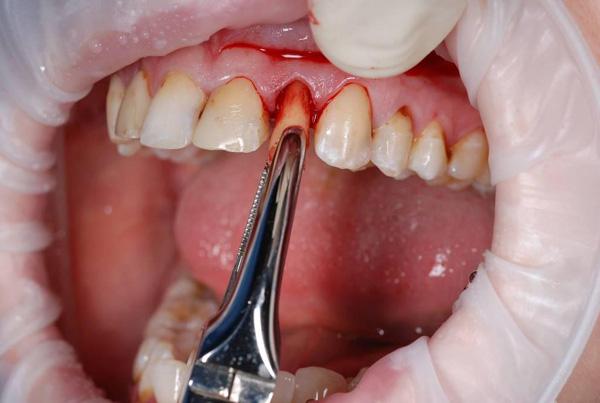

Фото 2. Сложная экстракция зуба мудрости. Так как он лишь слегка виден на поверхности, то хирургу сперва приходится разрезать десну, а затем извлекать по частям.

Хирургическое

Хирургический способ применяется, когда необходимо удалить труднодоступные зубы. Применяется в основном при проблемах с прорезыванием и сильном разрушении зубов.

При хирургическом вмешательстве одними щипцами не обойтись, и врач прибегает к скальпелю, производя рассечение слизистой оболочки и надкостницы.

Минус данной методики: операция может трудно переноситься, долго заживает ранка. Плюсы: удаляются труднодоступные зубы, с кистами, сильно разрушенные.